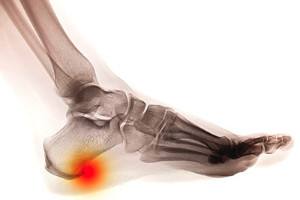

Patients who have developed a bone spur are often aware of the pain and discomfort it can cause. Heel spurs that develop on the bottom of the heel is classified as heel spur syndrome. When a bone spur forms at the back of the heel at the point where the Achilles tendon fits into the bone, it is known as insertional Achilles tendonitis. Heel spurs can develop as a result of frequently participating in running and jumping activities that can overstretch the plantar fascia. Limited range of motion can occur with Achilles tendonitis, and it may be more common among patients who are middle-age. If you have pain in your heel, it is strongly suggested that you consult with a podiatrist who can diagnose heel spurs, and offer the correct treatment for you.

Heel spurs are formed by calcium deposits on the back of the foot where the heel is. This can also be caused by small fragments of bone breaking off one section of the foot, attaching onto the back of the foot. Heel spurs can also be bone growth on the back of the foot and may grow in the direction of the arch of the foot.

Older individuals usually suffer from heel spurs and pain sometimes intensifies with age. One of the main condition's spurs are related to is plantar fasciitis.

The pain associated with spurs is often because of weight placed on the feet. When someone is walking, their entire weight is concentrated on the feet. Bone spurs then have the tendency to affect other bones and tissues around the foot. As the pain continues, the feet will become tender and sensitive over time.